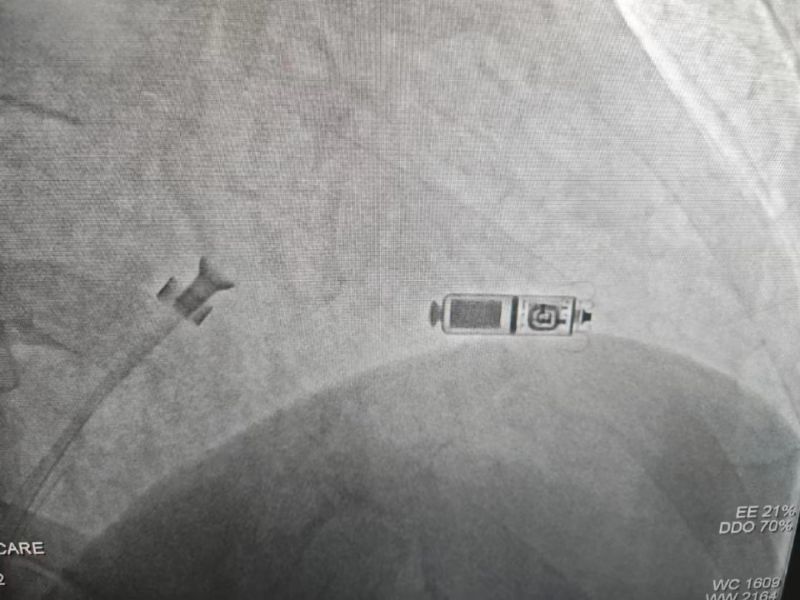

手術過程:經過充分的術前討論,在延安大學咸陽醫院心血管病院吳棟梁院長、劉雄濤副院長的指導與支持下,李陽教授、何克強主治醫師、辛浩主治醫師與導管室介入團隊的共同努力下,經過超聲科、心電中心等多學科協作,成功為患者植入雙腔無導線永久起搏器,術后第二天患者在起搏器保障下經藥物治療恢復正常的竇性心律。目前患者心臟情況及腦梗均恢復良好,已順利出院。

科普:Micra無導線起搏器號稱“世界最小起搏器”,無需植入心內膜導線,也無需在胸前皮下制作囊袋放置脈沖發生器(起搏器),手術僅需局部麻醉,通過股靜脈穿刺,將起搏器經導管植入心腔內,手術時間短,減少出血、血腫及感染風險,術后恢復快,肢體活動不受限,無異物感。

優勢:比傳統起搏器體積減少93%,體積更小,重量僅2g,類似一顆維生素膠囊;雖體積只有傳統起搏器十分之一,但其小小身體儲存大能量,續航時間超過12年,整個手術過程平均約30分鐘,植入成功率高,術后8-12小時即可下床活動,術后1-2天即可出院;兼容1.5T(特斯拉)/3.0T全身核磁共振掃描。滿足患者植入Micra之后疾病的診斷和治療需求。